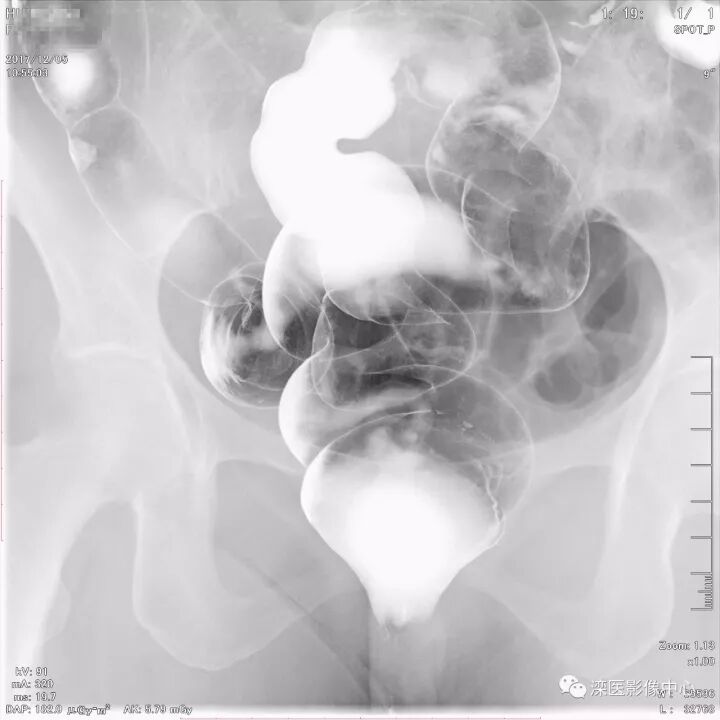

下面请您审阅近期我院影像科开展下消化道双对比造影检查的图像:

(以上图像多角度显示直肠、乙状结肠)